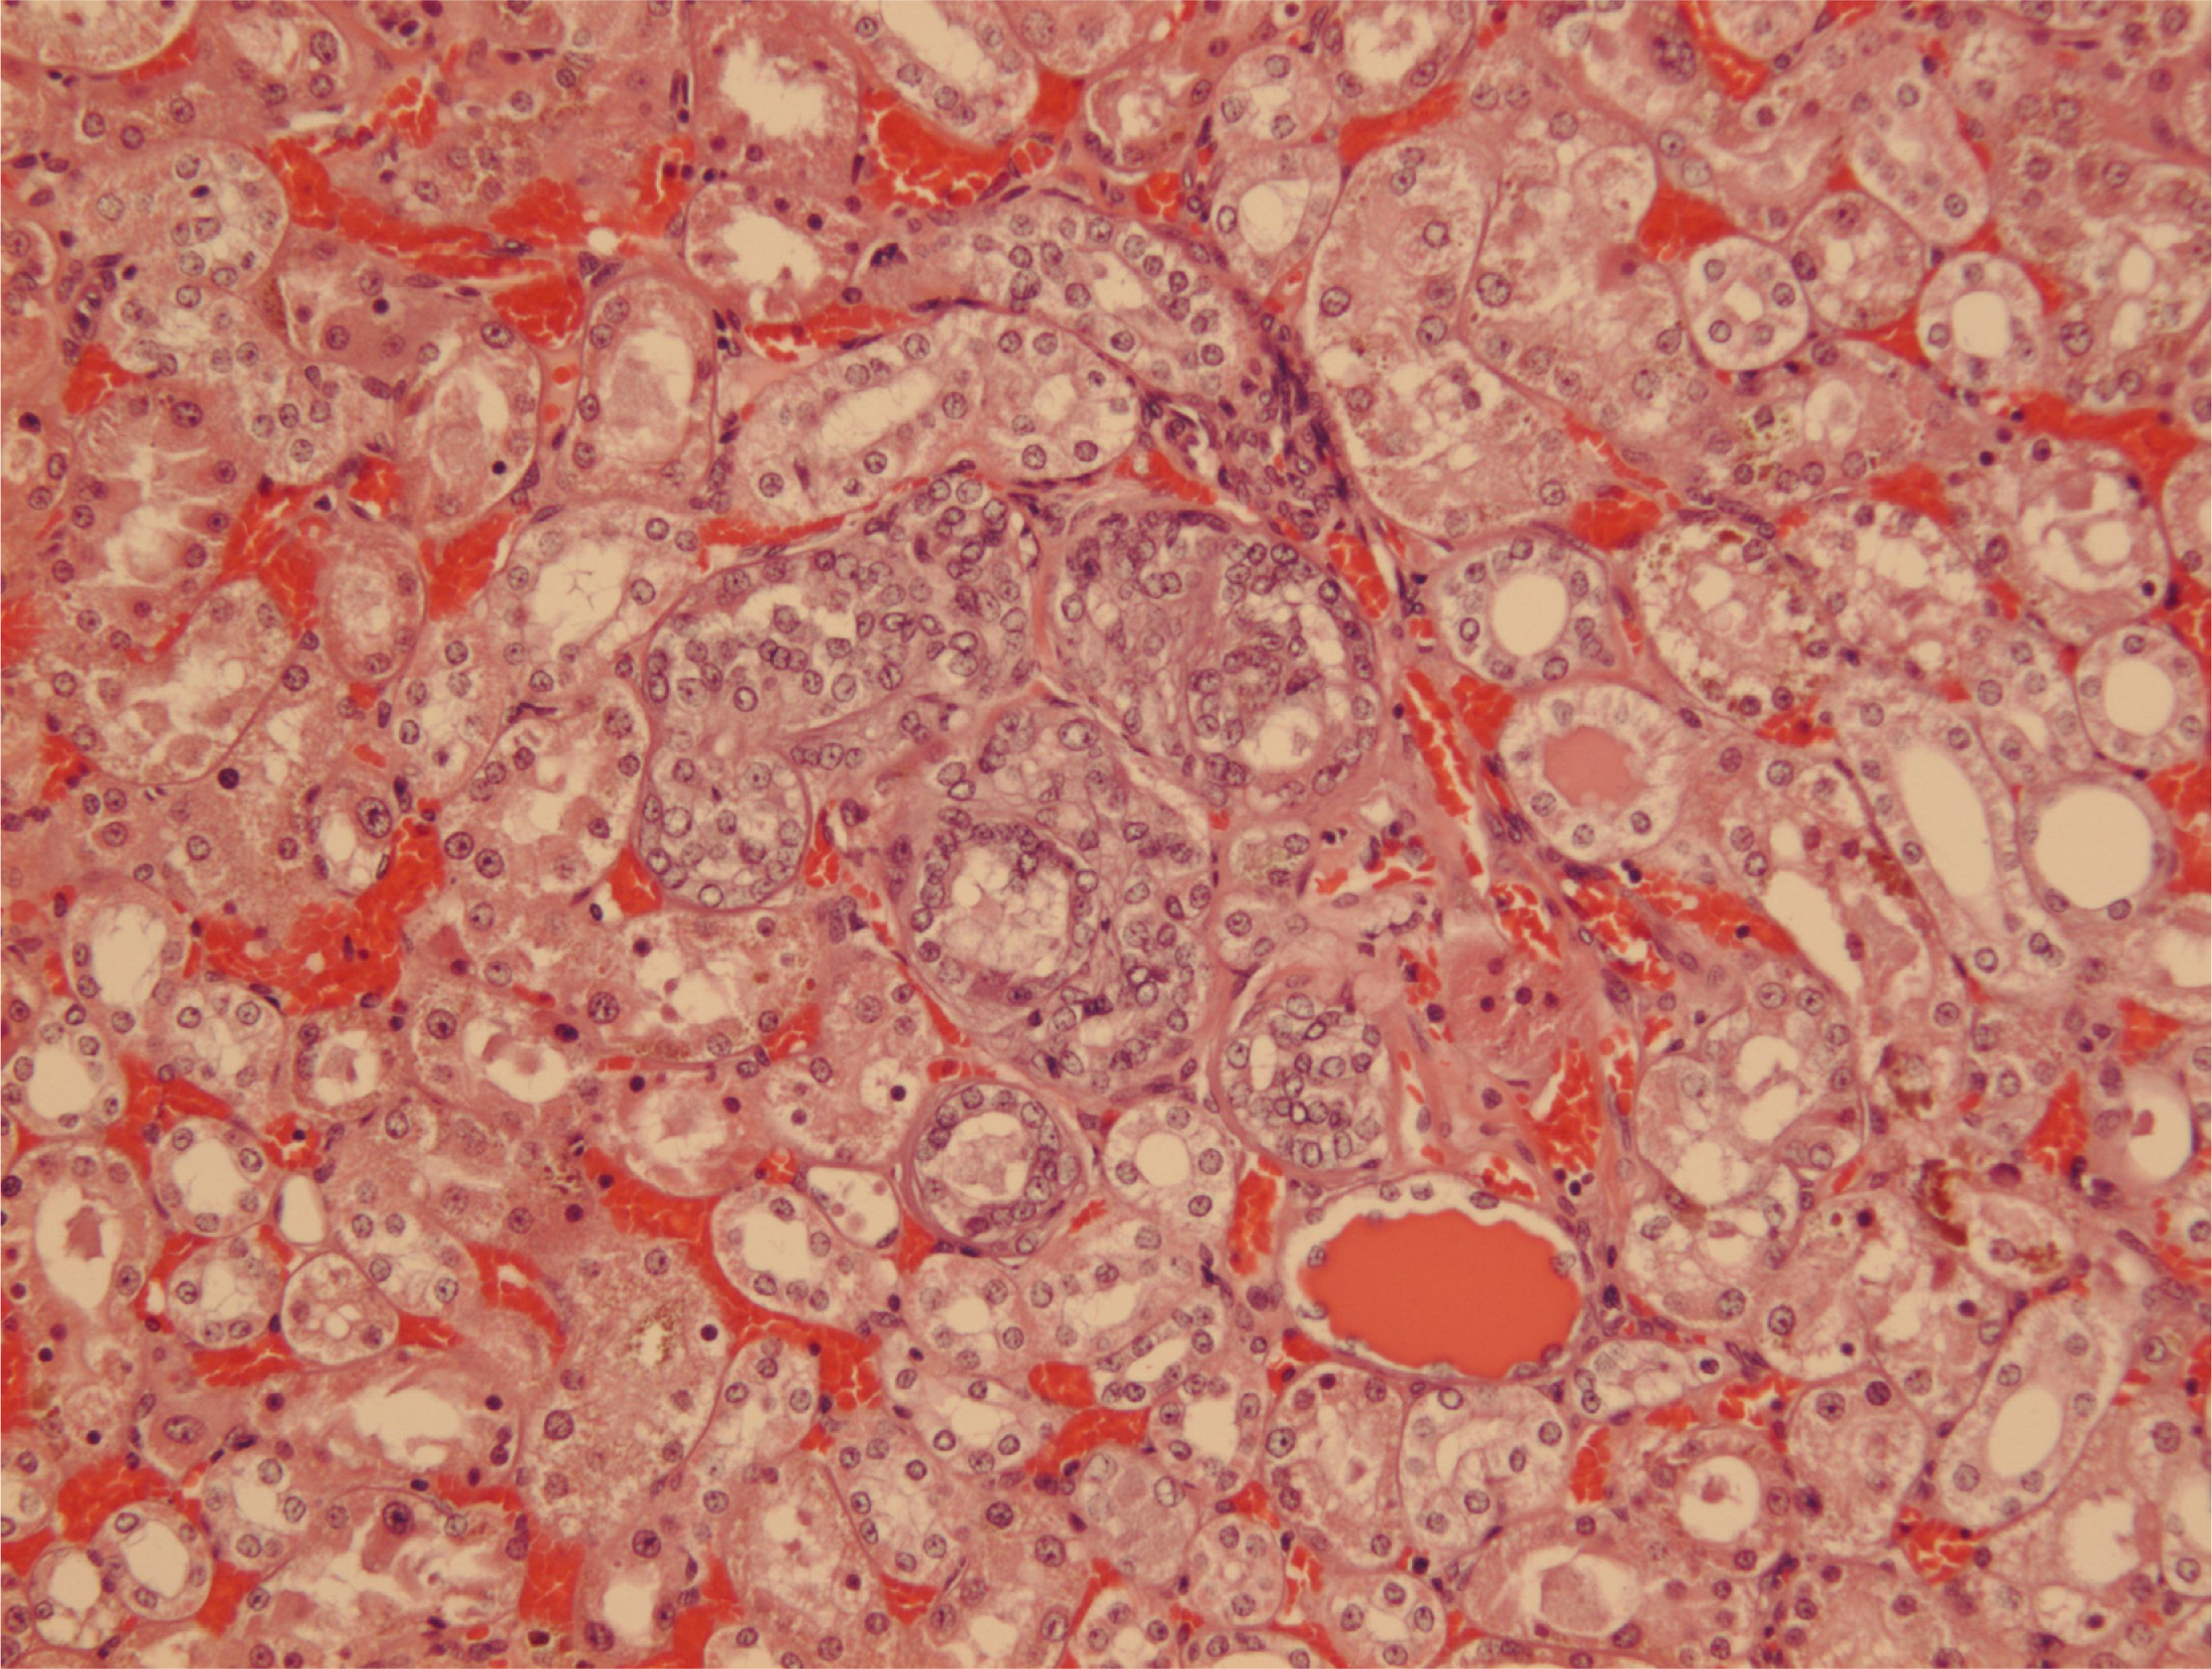

Courtesy of NTP Archives, we have been able to review H & E sections of the tumourous kidneys of Fischer females from the OTA study and study all the benign and malignant hyperplasias. Comparison with the more obvious tumours in male rats, reported in the NTP study and also illustrated from recent experiments [16, 17], can be made from the example shown in Figure 3AB. In contrast, Figure 3C shows the magnitude of the largest (4mm diameter) carcinoma in female rats of the NTP study, and which did not even distort the kidney. Nevertheless, detailed histopathology shown in Figure 4A, B illustrates that there was typical disorganised carcinoma with many enlarged nuclei with prominent nucleoli, infiltrating surrounding renal parenchyma and reminiscent of that of male rat renal carcinomas in which DNA ploidy distribution has been measured as consistently aneuploid [16]. A surprising observation was extensive kayomegaly focused within the renal papilla of all female rat tumour-bearing kidneys of the high OTA dose group, where the section passed though the papilla (Figure 4C). This does not seem to have been reported before, but in the present context is interpreted as consequential in the female of a smaller proportion of excreted OTA, being transported into proximal tubule epithelia than in the male. Some free OTA in glomerular filtrate may then have been available to affect epithelia in the loop of Henle. Since the carcinomas were all unilateral and microscopic, and were discovered only at the end of the study, they were most unlikely at that stage to have significantly affected health. Another, even smaller carcinoma is shown in Figure 4D. None of the three carcinomas had metastasised.

Since illustration of female renal tumour histopathology ascribed to OTA has not previously been published, location of a small cortical neoplasm is illustrated in Figure 5 to show its origin close to innermost glomeruli, but karyomegalies typically caused by OTA are nearby.

Another example has karyomegalic nuclei already located amongst proliferating epithelial cells (Figure 6). The other few small solitary renal neoplasms in females at or near the 2 year endpoint of the NTP study seemed all to be located in the corticomedullary region (e.g. Figures 7 and 8).

Figure 4. Micrographs of H & E sections of NTP female high OTA dose Fischer rats. A-C, detail of section in Figure 4C. A, representative carcinoma. B, carcinoma infiltrating renal medulla. C, prominent karyomegaly in the renal papilla. D, another example of a small renal carcinoma with necrotic centre, located at the corticomedullary junction.

Figure 5. NTP female (105 weeks, high OTA). Focal adenoma sited just inside the innermost glomeruli. Karyomegalic nuclei are located between tumour and glomeruli.

Figure 6. NTP female (91 weeks, high OTA). Small cluster of renal tubules with epithelial proliferation, constituting adenoma containing several karyomegalic nuclei.

Figure 7. NTP female (104 weeks, high OTA). Prominent karyomegalic nuclei and mitosis in cytomegalic epithelium of inner-cortical tubule. Karyomegalic nuclei also in some surrounding tubules. Possibly a very early tumour.

Figure 8. NTP female (104 weeks, high OTA). Nuclear proliferation in an inner-cortical tubule with karyomegalic nuclei in adjacent and nearby tubules. Probably an early adenoma.